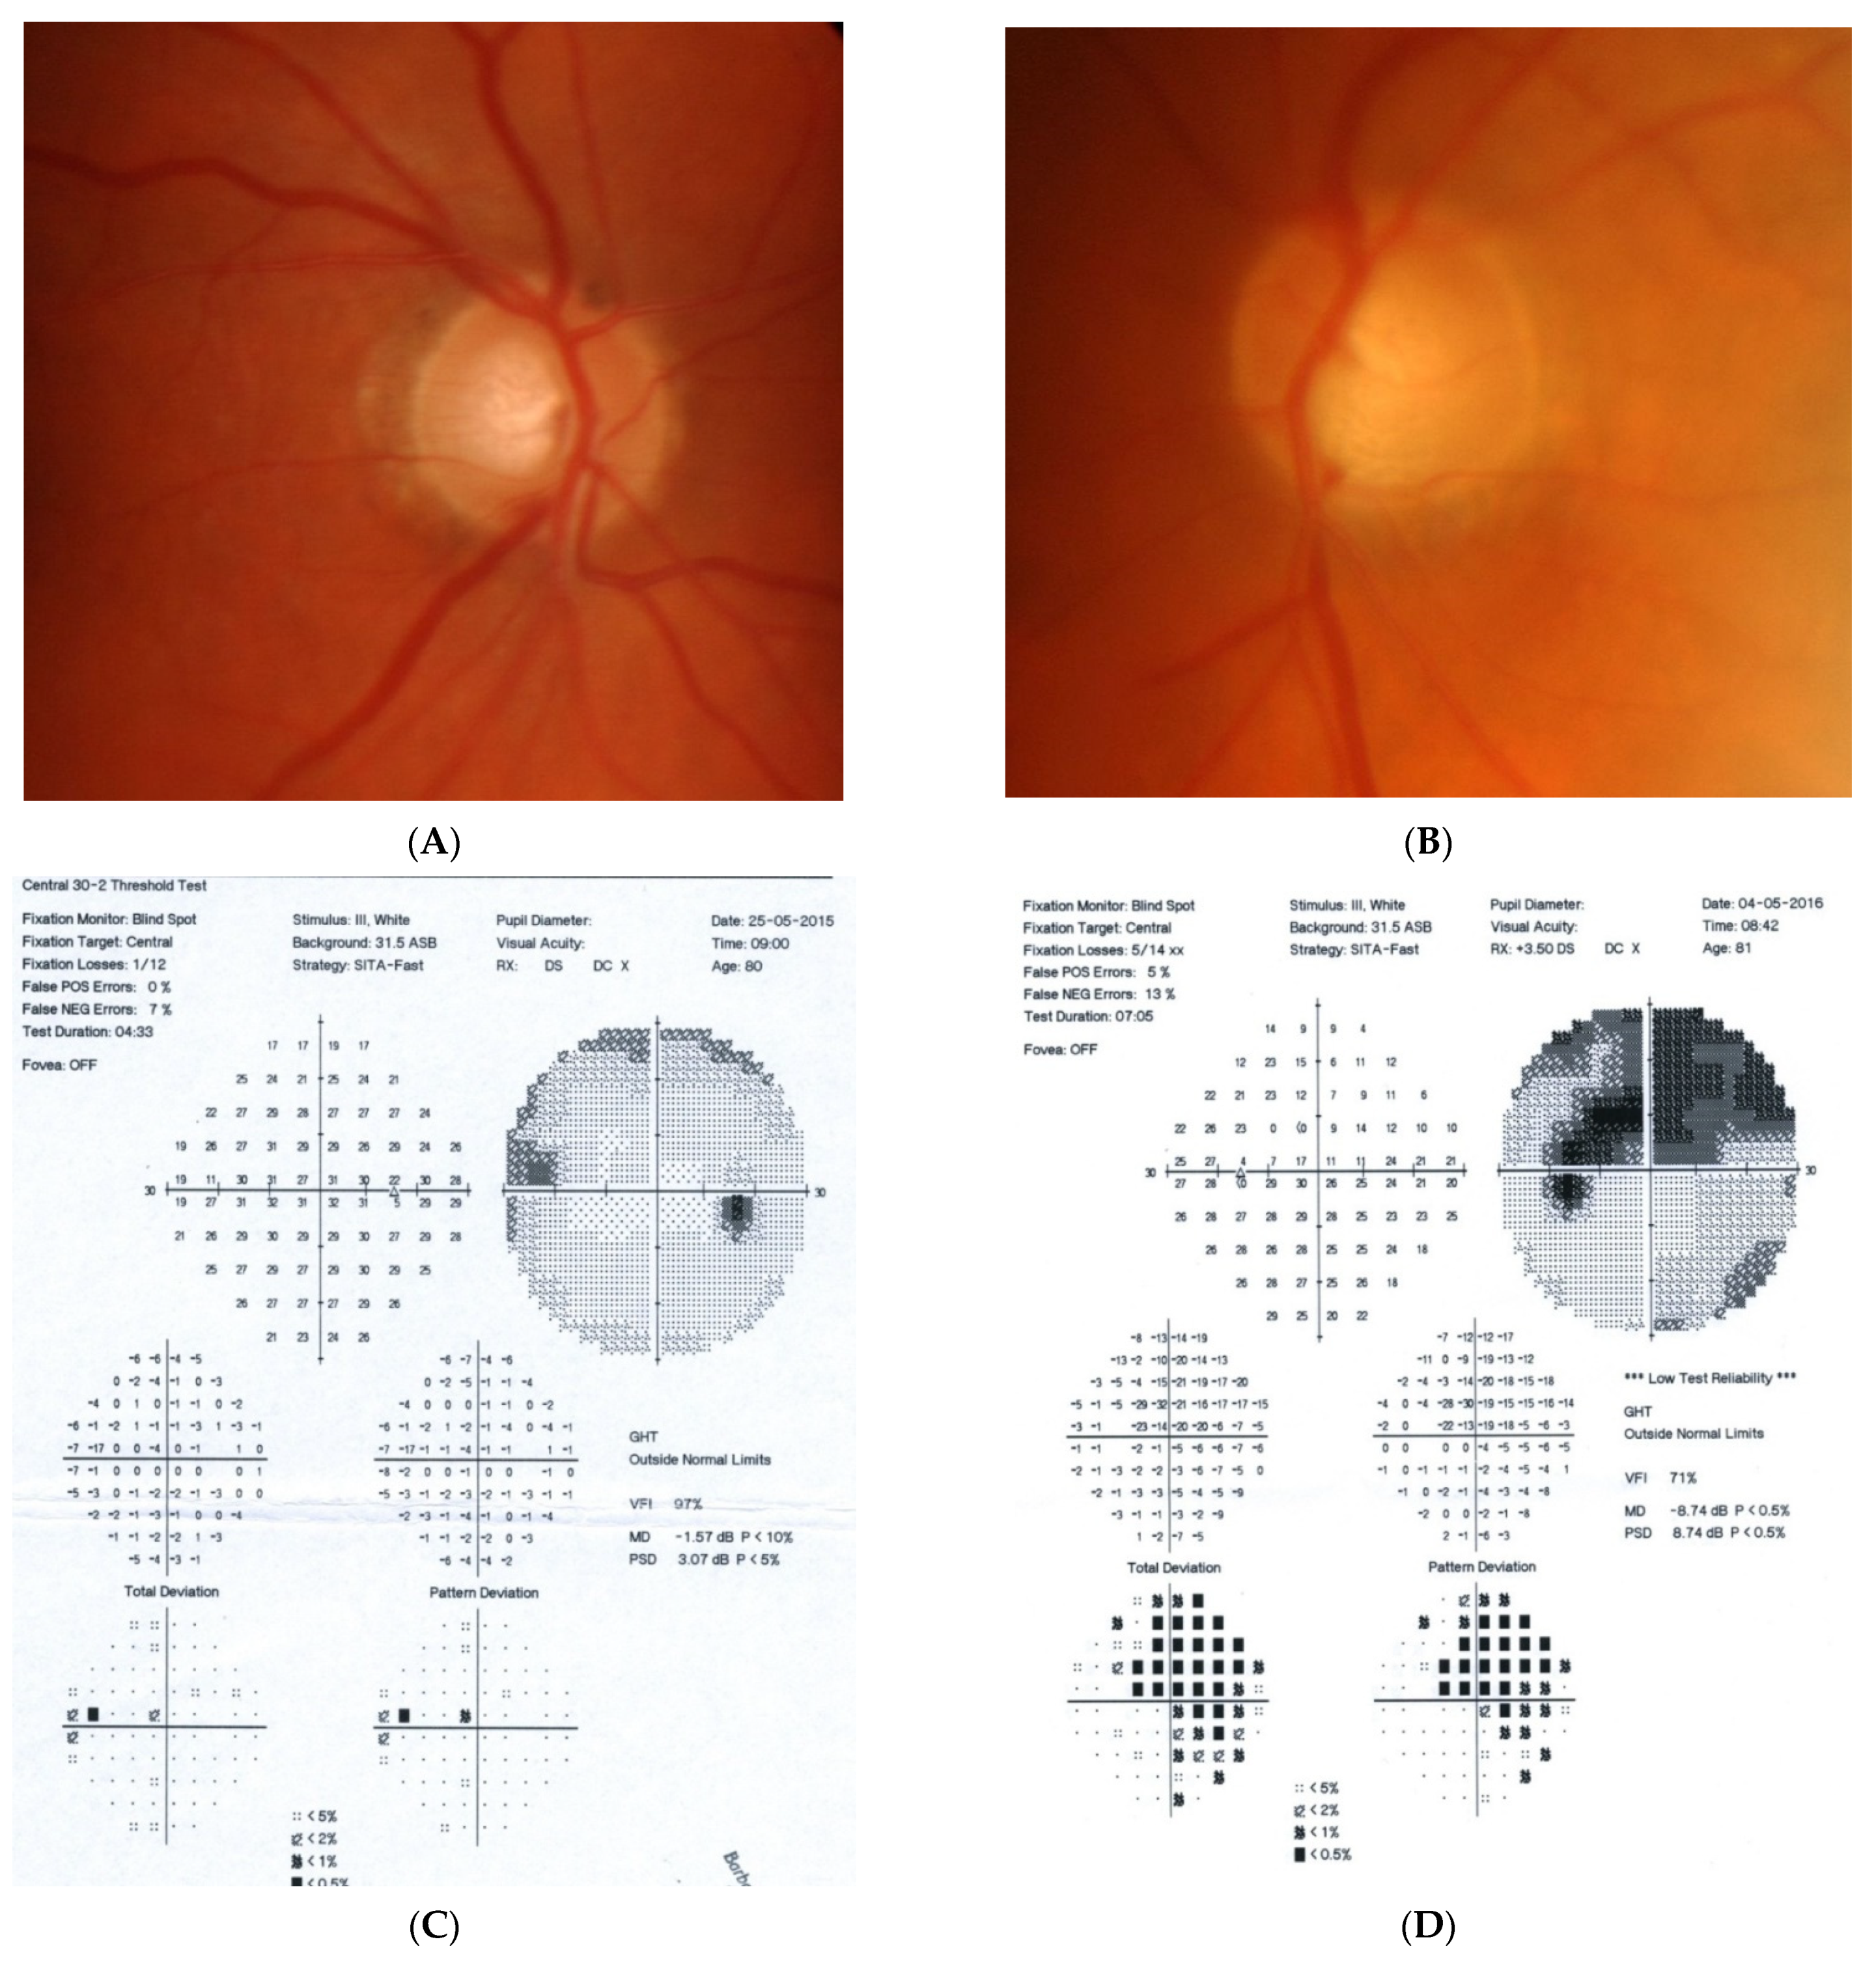

2.1. Case 1

2.2. Case 2